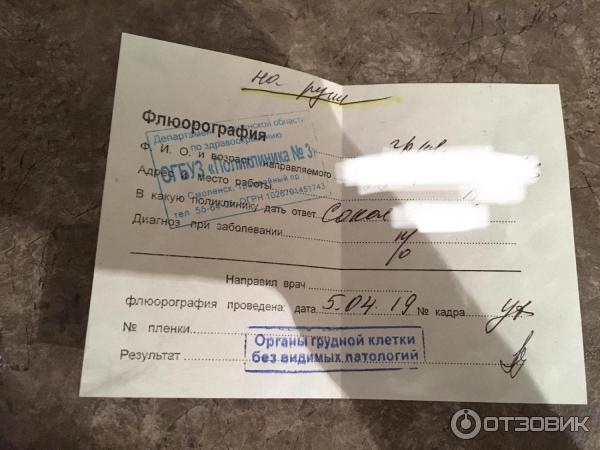

Влияние излучения при флюорографии: что нужно знать?